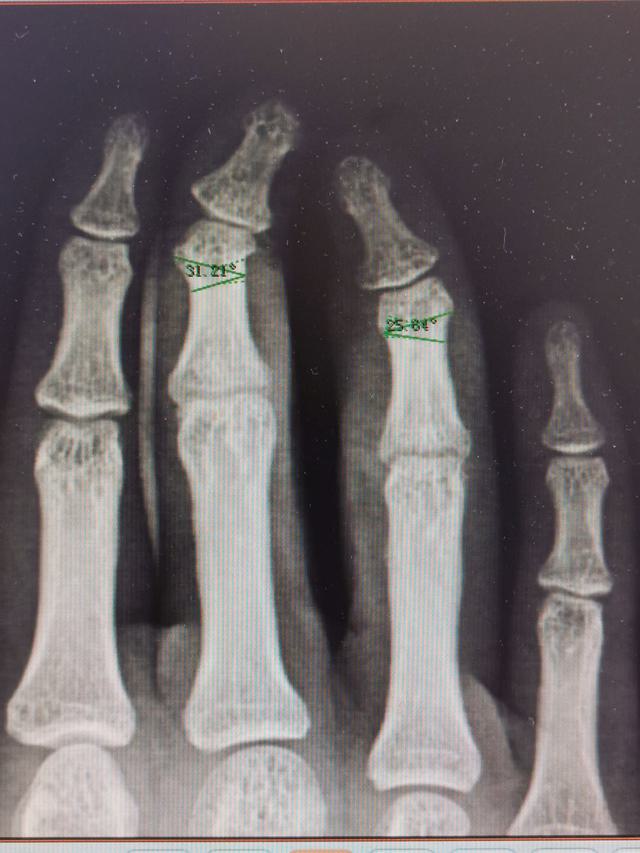

门诊收治的病人

4岁时行并指分指手术

目前患者19岁

诉求:

1、掌侧瘢痕挛缩,2、DIP侧偏畸形,3、PIP伸直受限

1.jpg

微信图片_20230717220435.jpg

微信图片_20230717220439.jpg

微信图片_20230717220442.jpg

解决第一个问题:瘢痕条索切除,Z字成形术

第二个问题:中环指中节指骨颈V形截骨,因为孩子的伸肌腱张力较高,选择闭合截骨(短缩)

第三个问题:PIP伸直受限,考虑为中央腱松弛所致,术中紧缩中央腱,松解中指PIP掌板